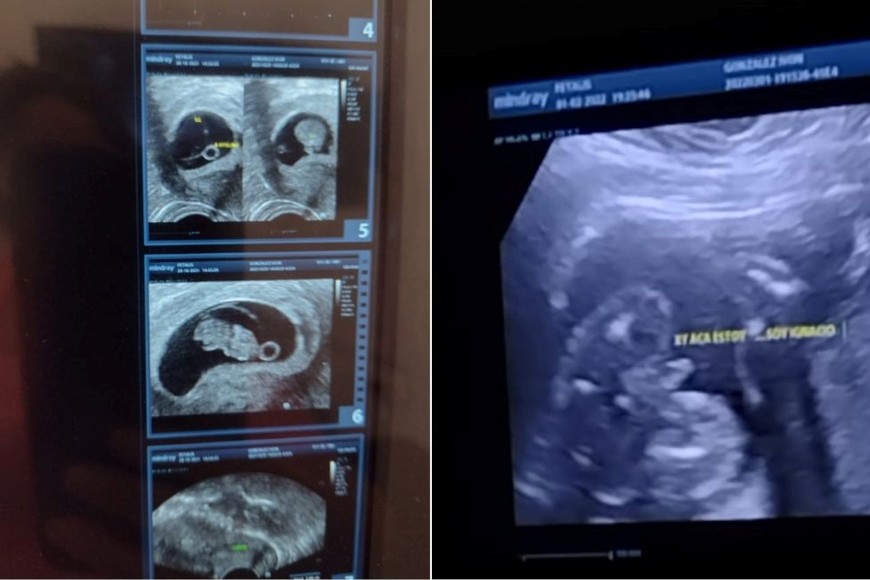

Y ese que quedó solito era Ignacio. El más fuerte y el más lindo, hoy está junto a sus padres, luego de tanta espera. “Cuando me lo mostraron era una gotita de agua en un vidrio, y hoy está acá”, afirmó Sergio.

La alegría se incrementó cuando una ecografía reveló que estaban esperando a un varón.

El nombre Ignacio ya estaba en sus vidas desde hacía mucho tiempo. Siempre supieron que iba a ser el nombre de su hijo, y lo encontraron como una señal en cada paso que daban.

Hasta una suelta de globos que manifestó el futuro. “En una suelta de globos de Fertife, hace 11 años, cuando salió la ley, teníamos que poner qué nombre le pondríamos a nuestro hijo. Nosotros escribimos "Ignacio Ismael”. Cuando nos enteramos de que iba a ser nene busqué la foto por todos lados”, relató Ivón.